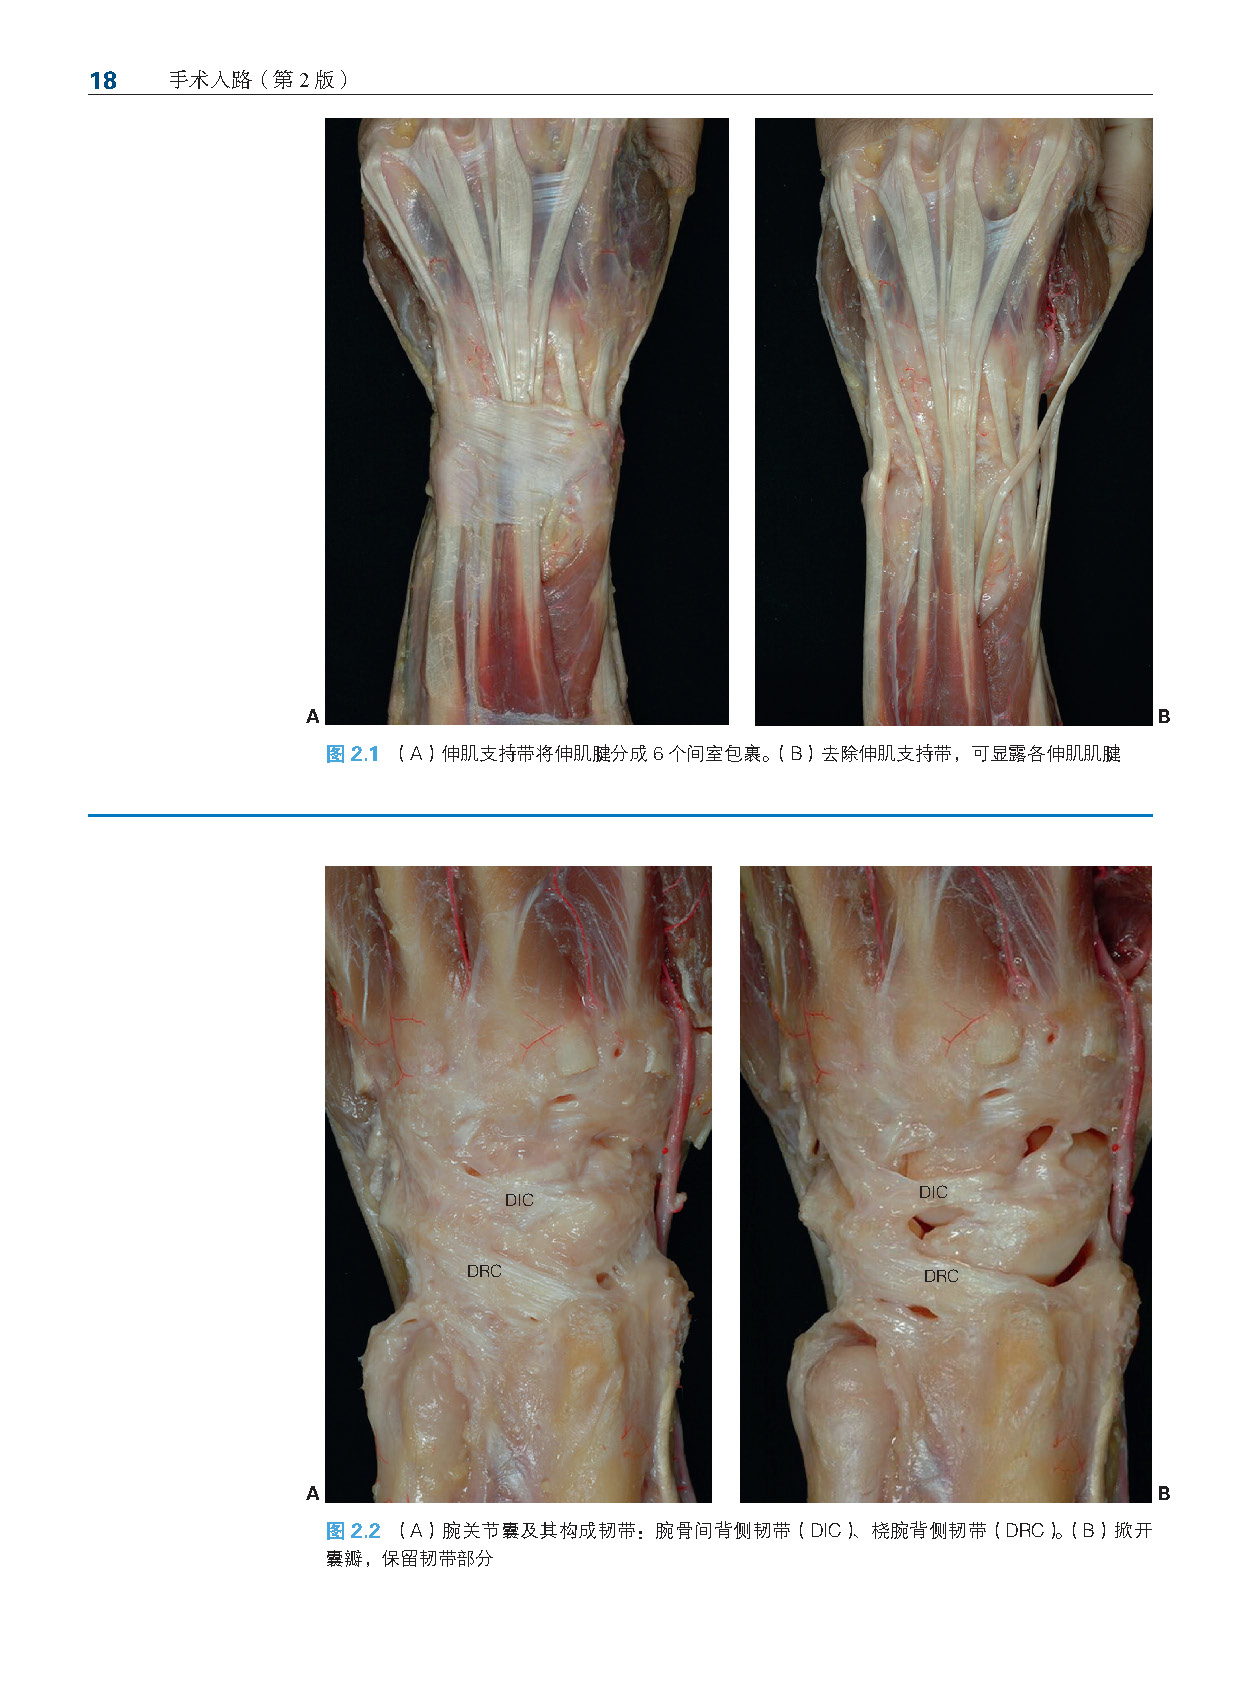

第2 章 腕关节背侧入路